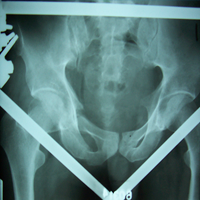

Case:8 Polytrauma

Patient having closed segmented fracture midshaft & lower 1/3 Tibia with closed fracture superior & inferior pubic rami right side with pelvis fracture following vehicular accident wastreated with intramedullary nail for fracture tibia and external fixator for fracture pelvis.

Pre-Op

Immdiate Post-op

Post-op Lateral

Ex fix with frame